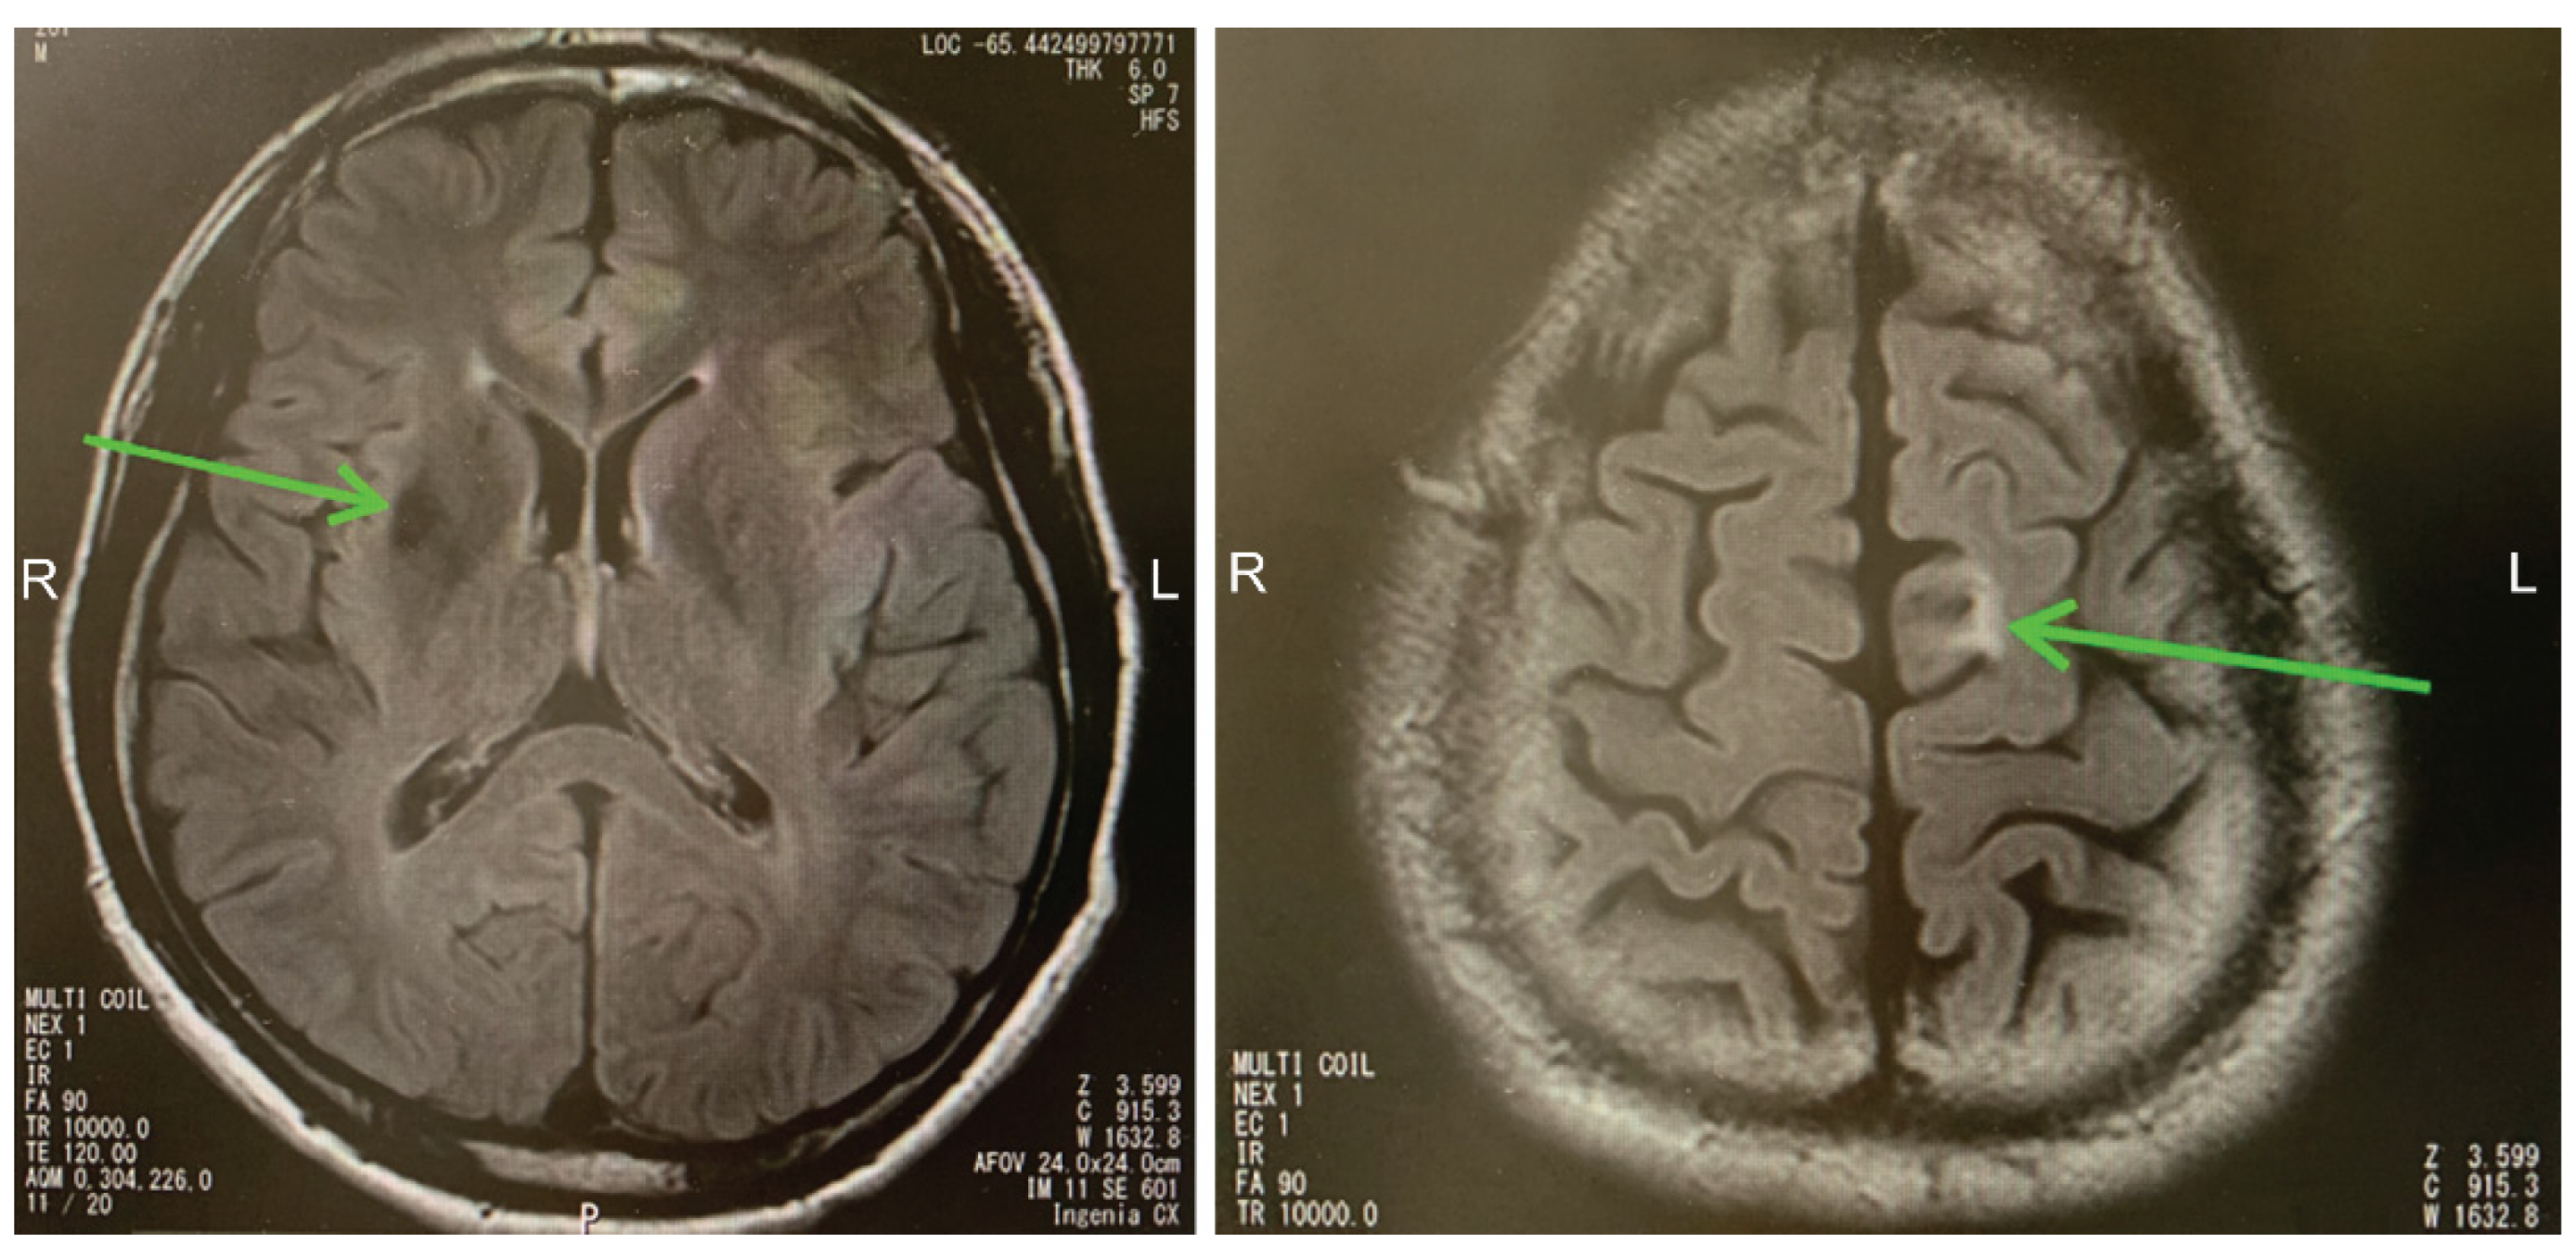

Patient 1 was a man who committed suicide after experiencing repeated episodes of sexual deviance. The patient was born healthy and had no remarkable medical history. He had acquired 12 years of education and had not exhibited any aberrant behavior, including sexually deviant behavior, prior to experiencing a TBI. At the age of 18 years, he was involved in a traffic accident and suffered a diffuse axonal injury (DAI); occipital bone fracture; acute epidural hematoma of the posterior fossa; multiple fractures of the mandible, upper and lower limbs, and spine; and disturbance of consciousness for approximately 1 month. Upon arrival at the emergency department, he had a Glasgow Coma Scale (GCS) score of E1V1M4; further, he immediately underwent endotracheal intubation due to tongue-base depression. He underwent a tracheostomy on day 14 of hospitalization and was transferred to our hospital for rehabilitation on day 43. On the 44th hospitalization day, he could follow simple verbal commands. Further, he was switched to a speech cannula and could speak briefly and weakly. No complicated behaviors were observed during his hospital stay. He received inpatient treatment for approximately 6 months in the acute care hospital and subsequently in the Convalescent Rehabilitation Ward of our hospital, and was discharged on the 221st day upon regaining his ability to independently perform his activities of daily living (ADL). Multiple neuropsychological examinations (Table 1) revealed that despite persistent mild attention disorder, the patient recovered normal intellectual function, with no further deterioration. His cognitive function was at the lower limit of normal, except for processing speed, on the Wechsler Adult Intelligence Scale 3rd edition (WAIS-III). The memory and executive function tests were within normal limits. Brain magnetic resonance imaging (MRI) performed 1 year after the injury (Figure 1) revealed a bilateral DAI of the frontal and temporal lobes, as well as a DAI of the right basal ganglia, splenium of the corpus callosum, and midbrain.

Figure 1. Brain magnetic resonance imaging (MRI) scans of Patient 1 show bilateral diffuse axonal injury (DAI) of the frontal and temporal lobes, as well as DAI of the right basal ganglia, splenium of the corpus callosum, and midbrain. Green arrows indicate major brain injury lesions.

The onset of disinhibition could be attributed to injury of the basal ganglia, which was observed on MRI/SPECT in both cases. Components of the basal ganglia include the corpus striatum (the putamen, caudate nucleus, and nucleus accumbens (located at the inferior end of the corpus striatum)), globus pallidus/subthalamic nucleus/substantia nigra, red nucleus, and lateral vestibular nucleus [11]. Both cases may have suffered damage to the nucleus accumbens, which is the pleasure center. Damage to the nucleus accumbens, orbitofrontal cortex (OFC), or inferior prefrontal cortex circuit (behavioral inhibition system), as part of the frontal basal ganglia thalamic circuit [12], may have resulted in the observed sexual disinhibition and alcohol abuse (dependence/addiction). There has been a growing interest in the indirect and hyper-direct pathways of the cerebral cortex–basal ganglia circuit as crucial neurological basis for behavioral inhibition in humans [13,14,15,16], which could have resulted in poor behavioral control in both cases. Alternatively, impulse control disorders could be linked to the nigrostriatal dopaminergic system. Under normal conditions of impulse control by the nigrostriatal dopamine system, the activity of dopamine neurons in the compact part of the substantia nigra increases in response to inappropriate behavior. This leads to an increase in neuronal activity in the caudate nucleus, a striate area that receives projections from the aforementioned dopamine neurons, which inhibits inappropriate behavior. Conversely, dysfunction of the dopamine system in the pars compacta of the substantia nigra or caudate nucleus results in an inability to suppress inappropriate behavior through these pathways [17]. In Case 1, MRI revealed DAI in the midbrain and right caudate nucleus; moreover, SPECT in Case 2 showed decreased blood flow around the midbrain. Therefore, the inability to suppress inappropriate actions could be attributed to a failure of the aforementioned system.